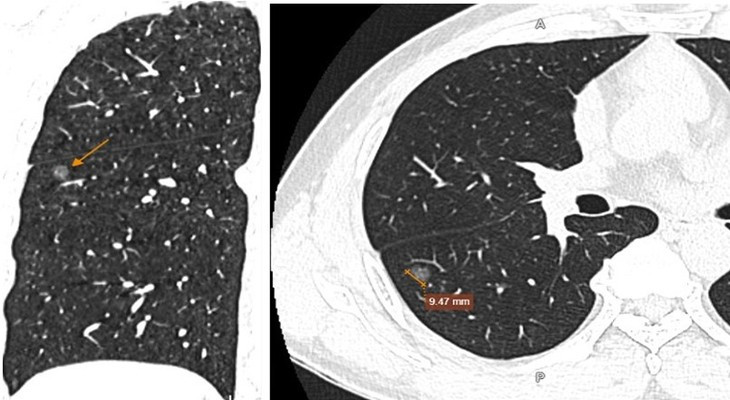

Tại đây, bệnh nhân T. được chỉ định làm các xét nghiệm và chẩn đoán hình ảnh cần thiết. Kết quả chụp cắt lớp vi tính (CT scan) cho thấy, hình ảnh nốt kính mờ phân thùy S6 phổi phải đường kính 9,5mm, kèm một số nốt rải rác nhu mô hai phổi, dày trung thất, dày màng phổi vùng đỉnh một bên, xơ vữa vôi hóa cung động mạch chủ, thoái hóa vài đốt sống ngực.

| Hình ảnh nốt kính mờ phân thùy S6 phổi phải đường kính 9,5mm, kèm một số nốt rải rác nhu mô hai phổi. Ảnh BVCC |

Với kết quả trên, bệnh nhân T. được khuyến nghị thực hiện thêm sinh thiết tổn thương phổi. Kết quả giải phẫu bệnh cho thấy tăng sinh các tế bào tuyến phổi không điển hình (AAH) - là tiền thân của ung thư biểu mô tuyến phổi.

Dựa trên kết quả lâm sàng và cận lâm sàng, bệnh nhân T. được chẩn đoán mắc tăng sản dạng tuyến không điển hình ở phổi.